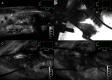

Bone devitalization is believed to be a critical determinant of complications such as infection or nonunion. However, intraoperative assessment of bone devitalization, particularly in open fractures and infections, remains highly subjective resulting in variation in treatment. Optical imaging tools, particularly dynamic contrast-enhanced fluorescence imaging, can provide real-time, intraoperative assessment of bone and soft tissue perfusion, which informs the tissues' ability to heal and fight infection. We describe a novel technique to apply indocyanine green-based fluorescence imaging, using a device that is frequently used in the operating room to assess skin or flap perfusion in plastic surgery, to assess bone and deep tissue perfusion in three pertinent cases: (1) a chronic infection/nonunion after a Gustilo type 3A tibia fracture (patient 1), (2) an acute Gustilo type 3C tibia open fracture with extensive degloving/soft tissue stripping (patient 2), and (3) an atrophic nonunion of the humerus (patient 3). In all three cases, fluorescence imaging (both time-specific fluorescence and maximum fluorescence) and derived kinetic maps of time-to-peak, ingress slope, and egress slope demonstrated clear spatial variation in perfusion that corresponded to the patient pathogenesis. The impact of this information on patient outcome will need to be evaluated in future clinical trials; however, these cases demonstrate in principle that optical imaging information has the potential to inform surgical practice, reduce the variation in treatment, and improve outcomes observed in these challenging patients.